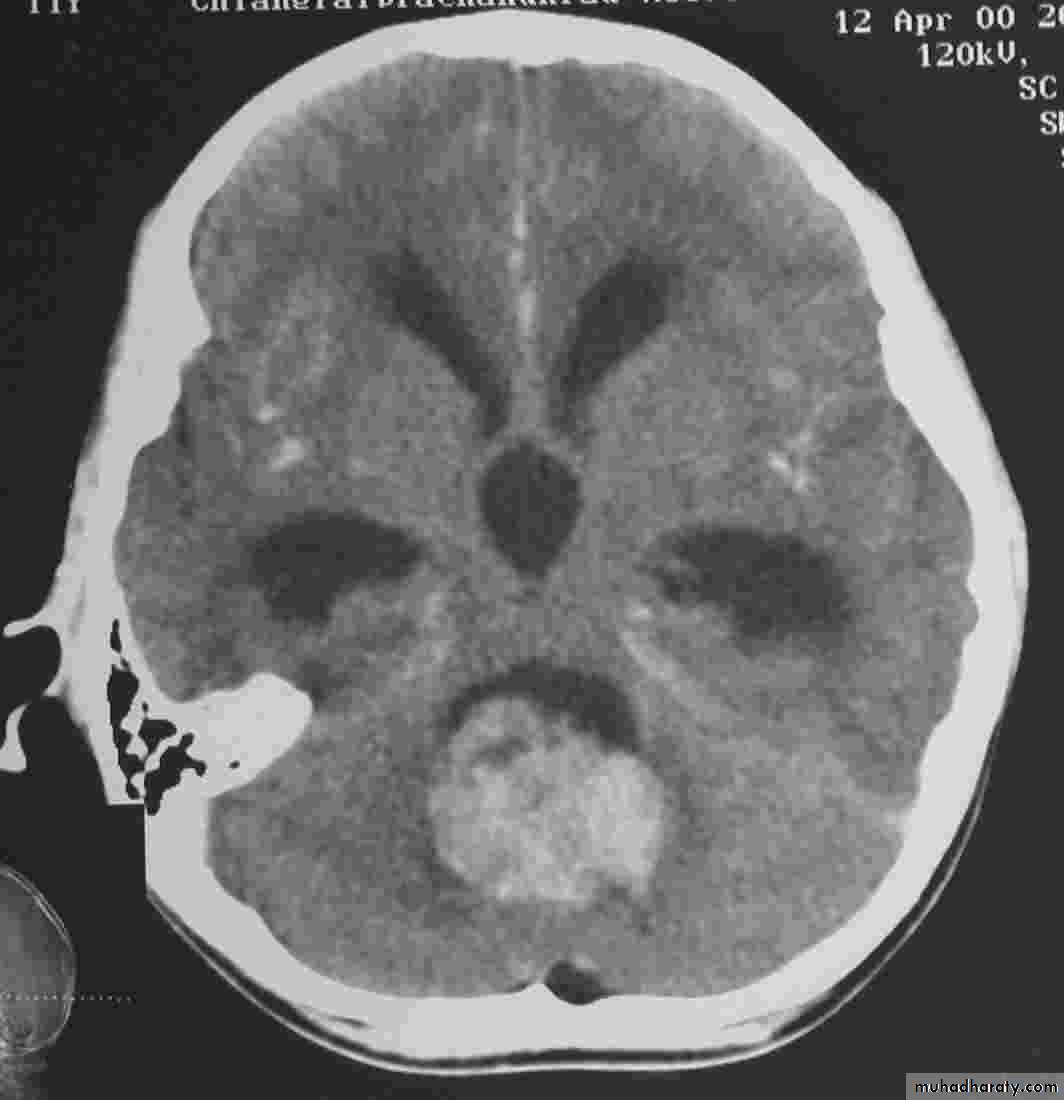

Posterior fosse tumor

Medullo blastoma

Age incidence between 5-15 Y represent about 35-40 %of PFT

Arise from the midline mainly within or from the roof of the 4 TH ventricle fill the fourth ventricle & seeding via the csf so can seen in the distal part of the spinal canal .

CT finding as well circumscribed lesion heterogeneous in density ,have solid & cystic part , with also scattered calcification little surrounded edema , the solid part is enhance

90 % present with obstructive hydrocephalous at the level of the 4Th V. with dilatation of the lateral V. ( body , frontal , temporal & third ventricle )

40 % of child have secondary metastasis at the time of presentation

Secondary metastasis

Old age group above 50 Y , any lesion within the cerebellar hemisphere it is secondary metastasis unless proven otherwise F. from breast CA M. from bronchogenic CA .

Appear as nodular single or multiple lesion hypo dense or hyper dense .

Surrounded by per focal edema

Enhanced as solid or ring pattern of enhancement .